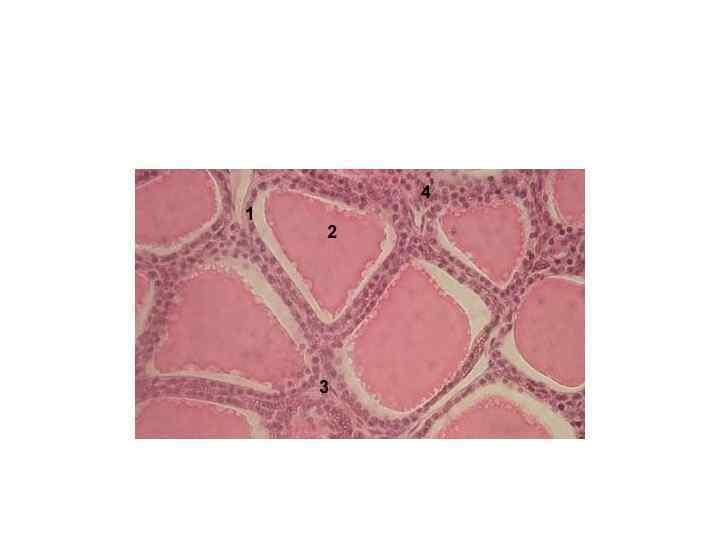

ФОЛЛИКУЛЫ ЩИТОВИДНОЙ ЖЕЛЕЗЫ

ФОЛЛИКУЛЫ ЩИТОВИДНОЙ ЖЕЛЕЗЫ